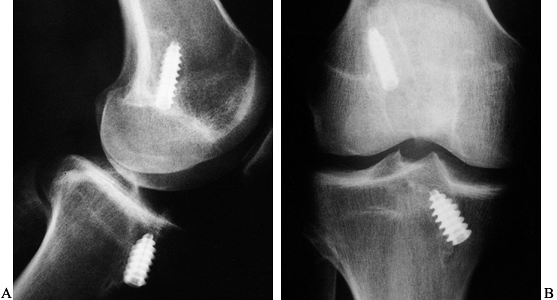

fracture, may be pathognomonic of ACL injury (Fig. 89.1) (121).

Figure 89.1. A:

Anteroposterior radiograph of a skeletally mature right knee with chronic ACL insufficiency. A healed Segond fracture is noted by the bony spur on the lateral tibial plateau’s lateral cortex, proximal to the fibula. B: Anteroposterior radiograph of a skeletally immature individual with a painful traumatic effusion. The x-ray reveals a lateral capsular avulsion, indicative of an injury to the ACL. |